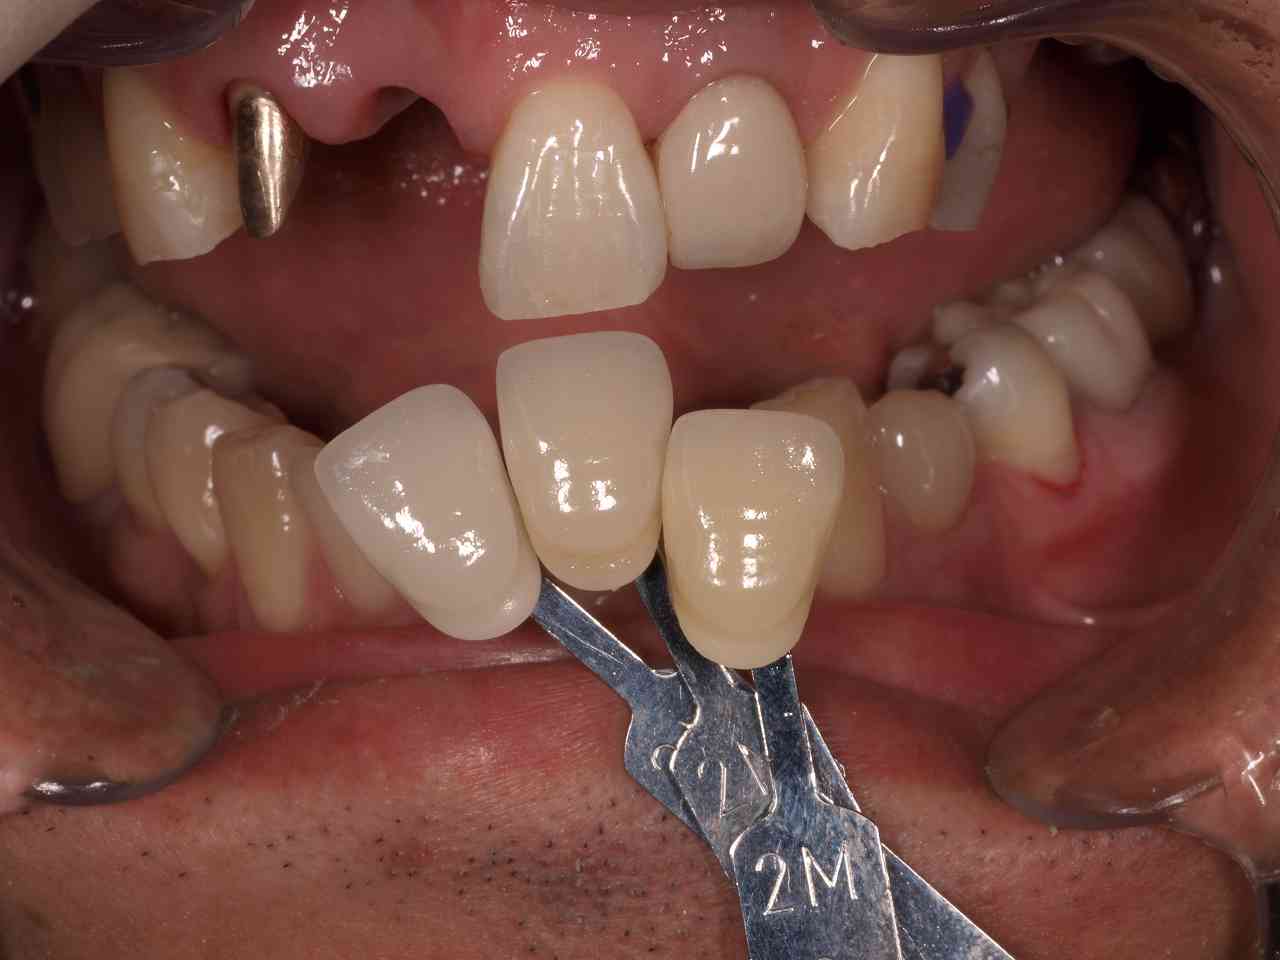

最終補綴になります

スポーツ選手なので一応、8番も残して大きく口腔内が変化しないようには配慮しています

このように入っています

臼歯部の安定を確認してから前歯部の最終補綴を行っています